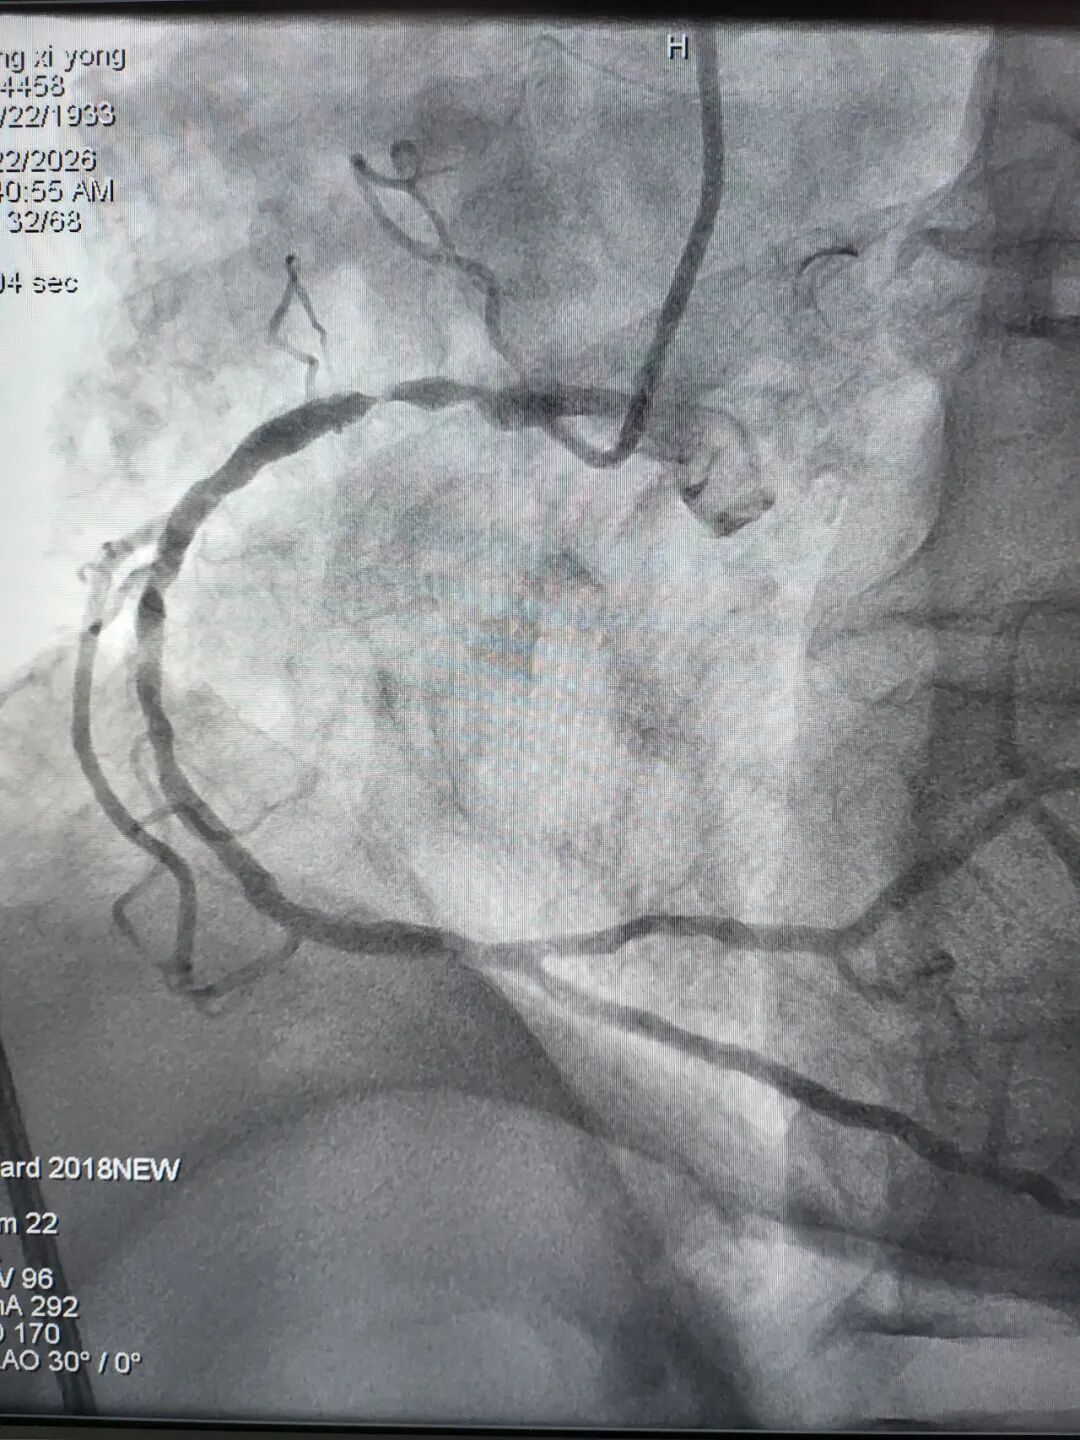

左前降支近中段CTO

右冠近段狭窄99%

左前降支近段狭窄99%

右冠近段次全闭塞

左前降支近中段弥漫性严重狭窄